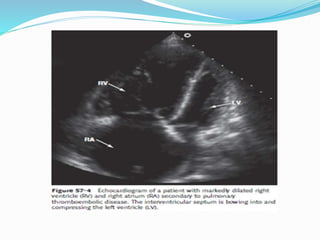

Echocardiogram

Transthoracic and transesophageal

echocardiography have limited use in the diagnosis

of PE. The sensitivity and specificity of these tests

are inadequate for diagnosis, because the offending

emboli are rarely proximal enough to be visualized.

A more important role of echocardiography in the

evaluation of patients with PE is that of risk

stratification.

Right ventricular dysfunction develops in association

with an acute PE. Worsening right ventricular function

relates directly to the degree the pulmonary vascular

bed is affected by the thrombus and, therefore, the size

of the embolic event. Some investigators have

suggested that more aggressive therapy, such as

thrombolysis, is indicated in patients with right

ventricular dysfunction emboli